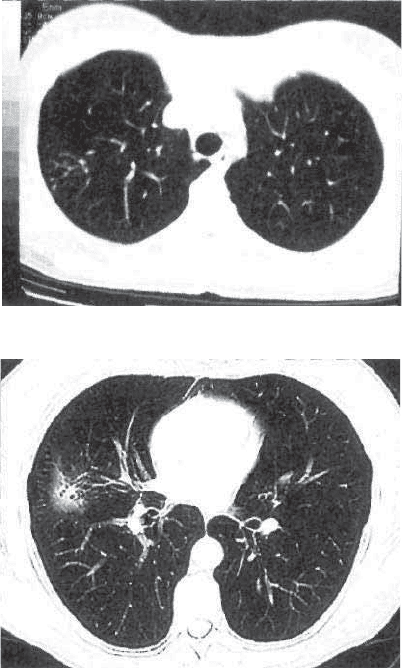

Рис. 10.6. Свежий очаговый

туберкулез легких. Полость

распада в очаге. КТ.